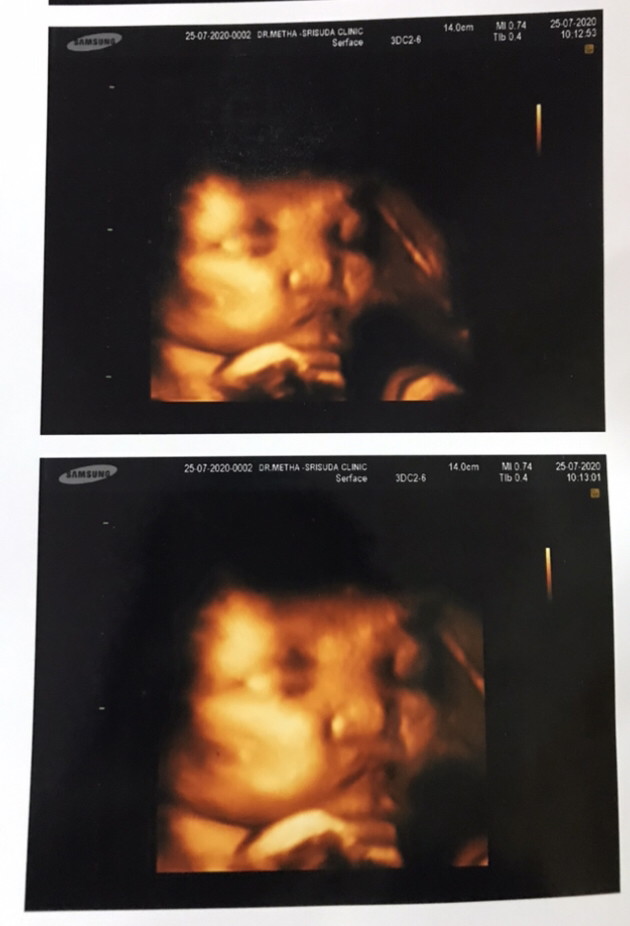

ตอน31 วีคค่ะ ลูกสาว

32 w 6d น้ำหนัก 2,600 ล่ะจ้า

ลูกสาว31วีคจ้าาา

28week ตอนนี้ 33+6weekค่ะ